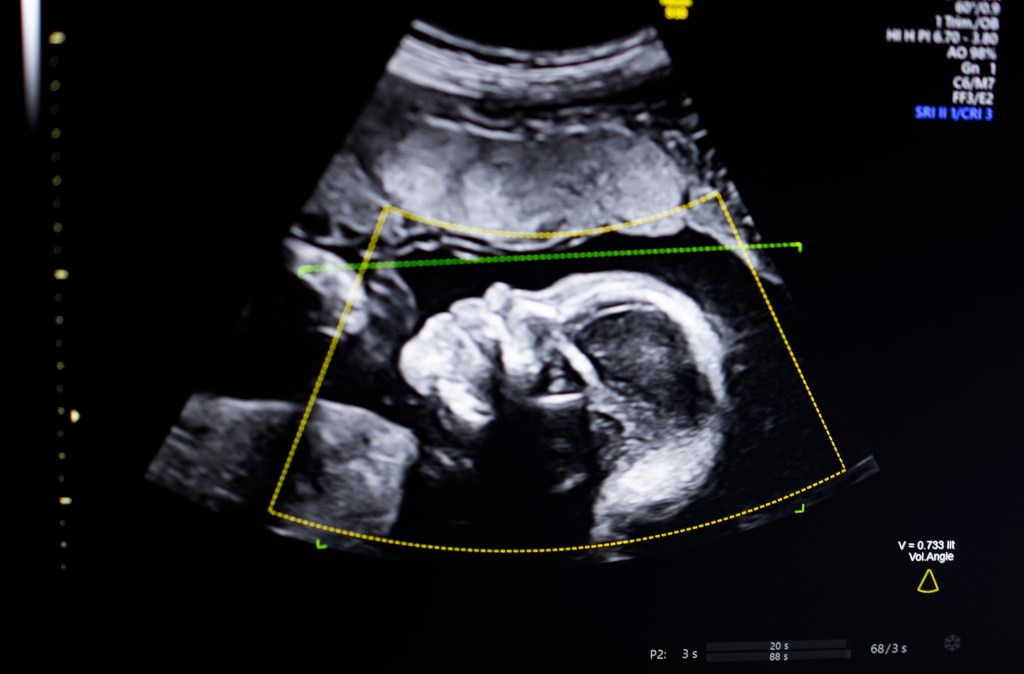

Image Credits:skaman306 / Getty Images

TechCrunch Disrupt Battlefield 2023 winner, BioticsAI, announced on Monday that it has received FDA clearance for its AI software that helps detect fetal abnormalities in ultrasound images.

The technology uses computer vision AI “to support fetal ultrasound quality assessment, anatomical completeness, automated reporting, and seamless integration into clinical workflows,” Bustami told TechCrunch.

Bustami said that the prenatal ultrasound has become the “cornerstone” of monitoring pregnancies, but its low-quality images can lead to misdiagnosis.